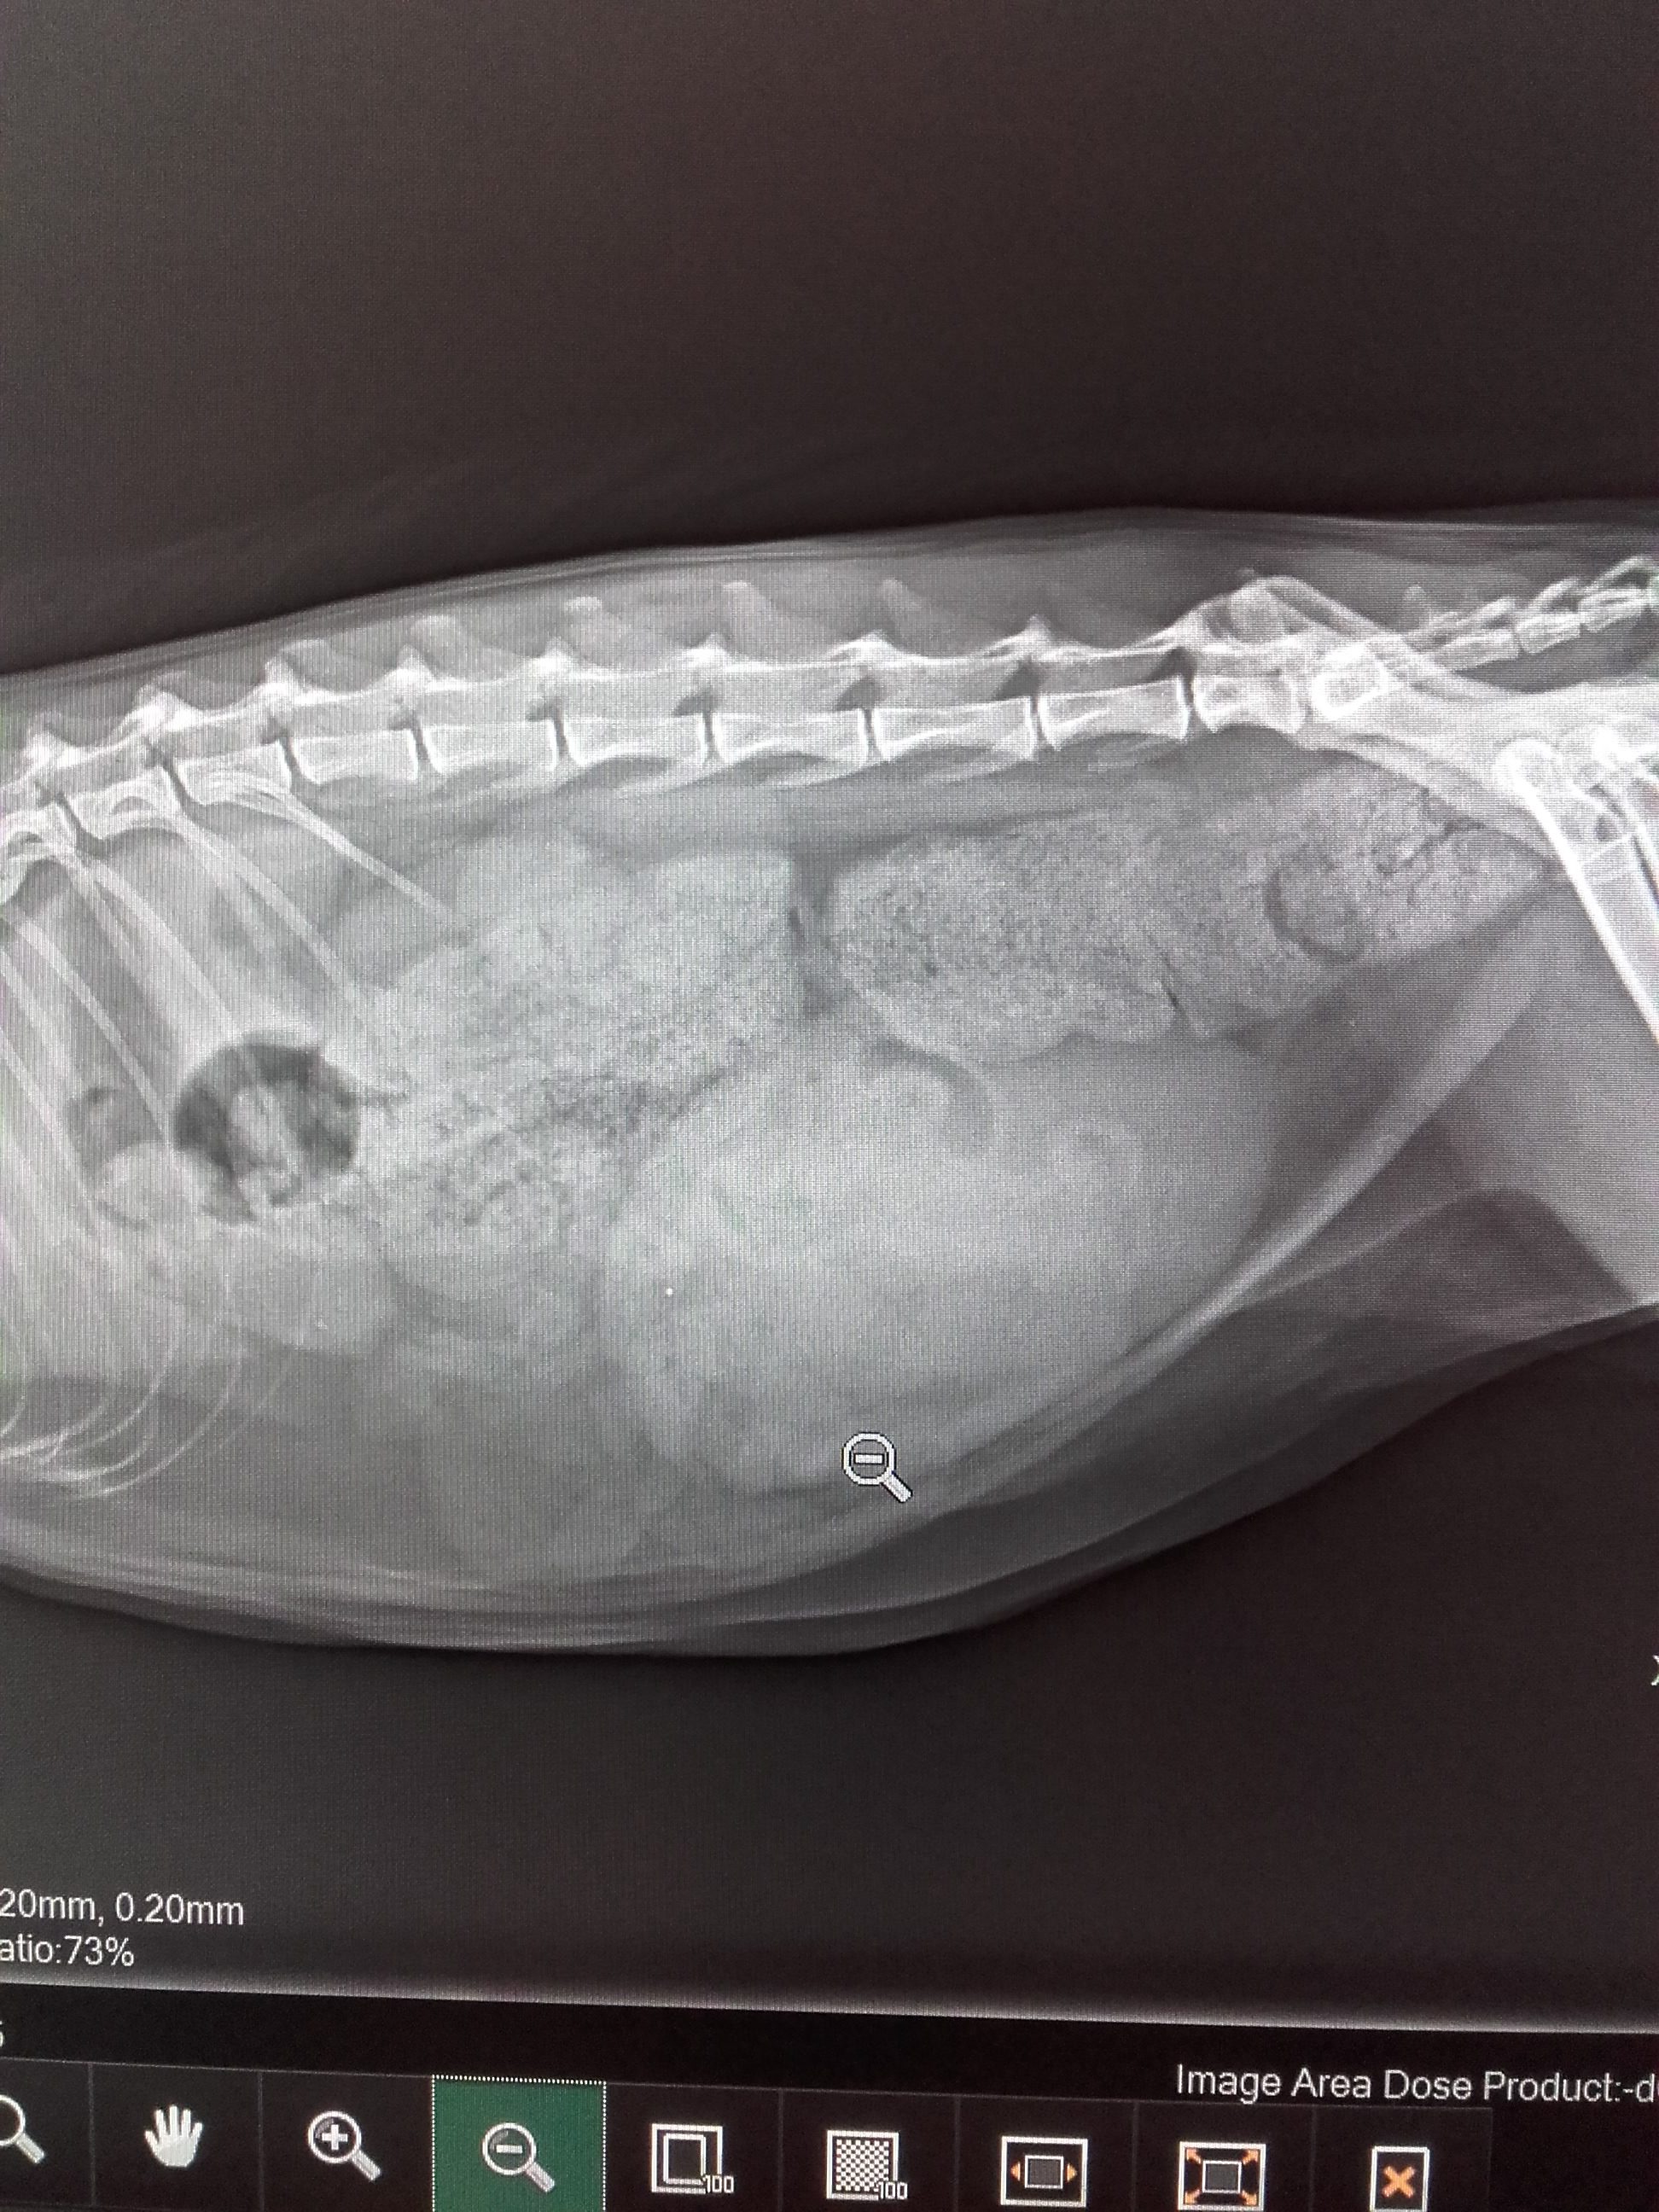

- Verstopfung bei einer Katze.